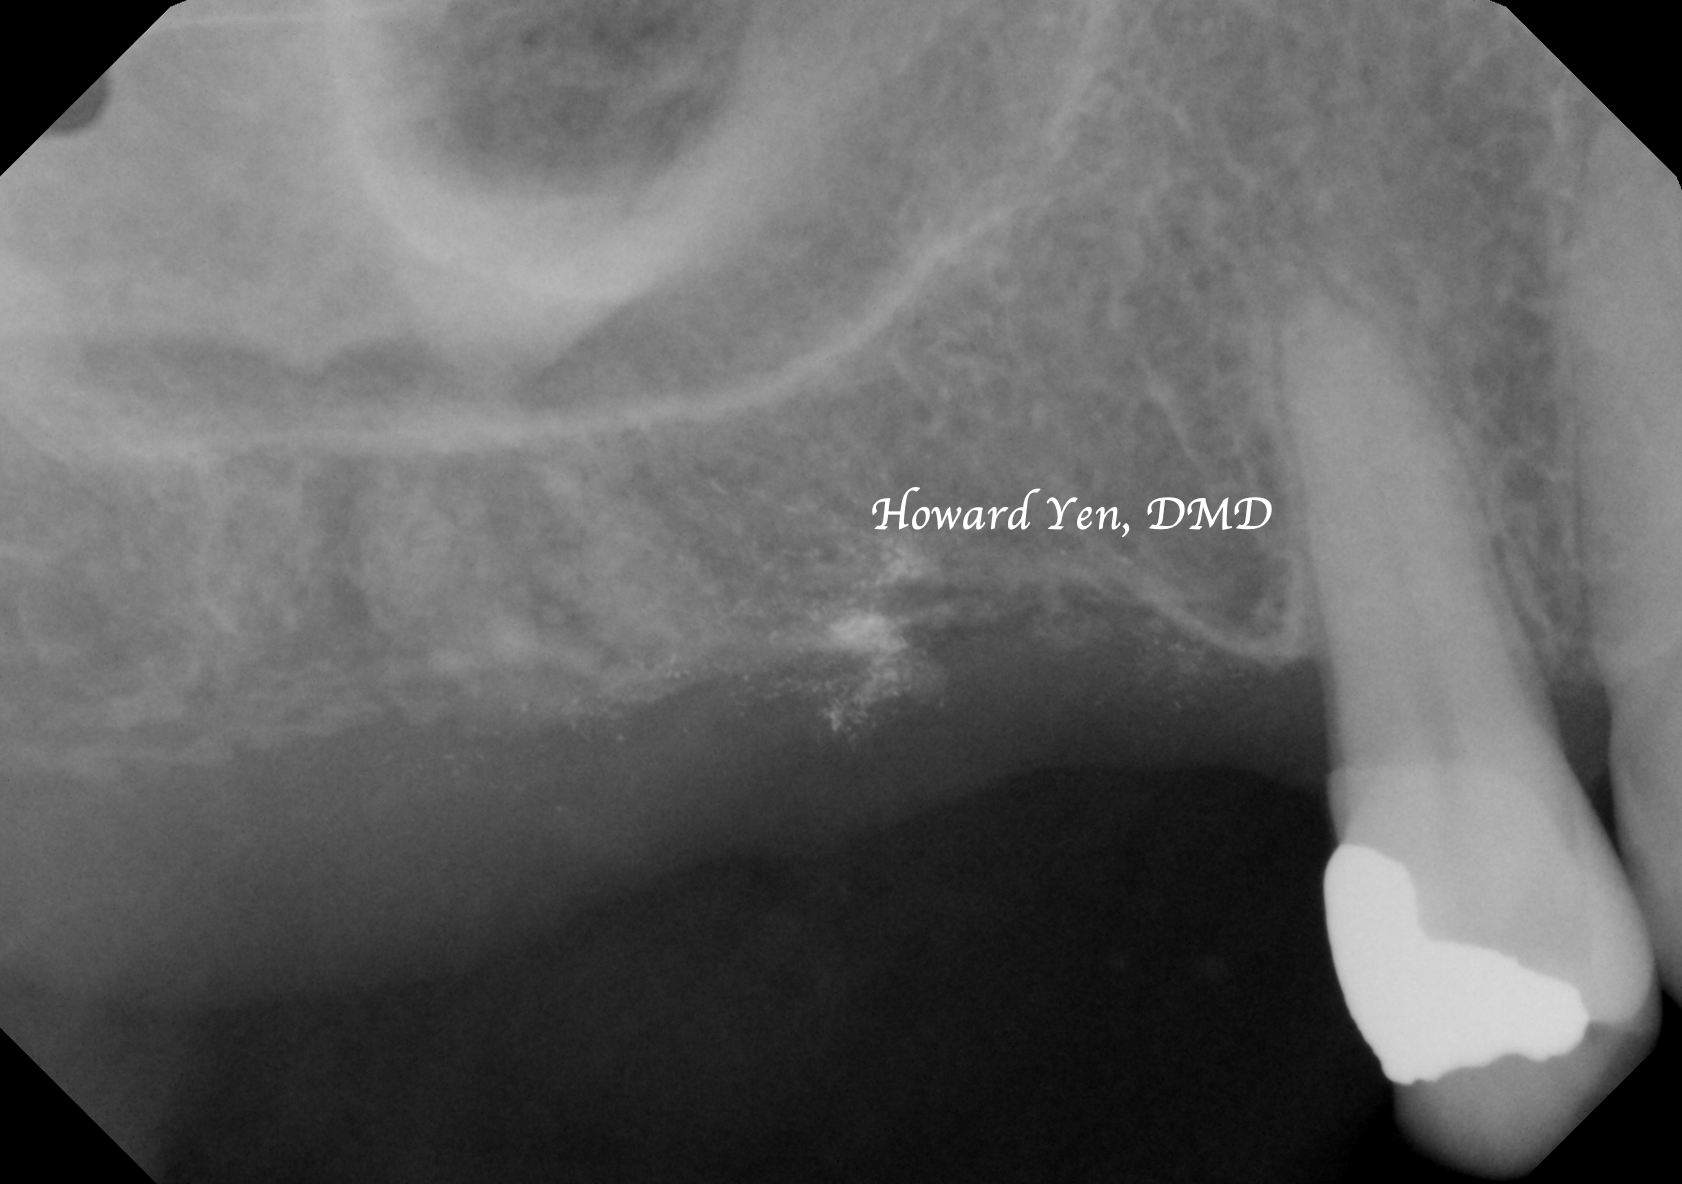

There’s the presence of maxillary sinus cavities around our nasal area and upper jaw bone. When an upper back tooth (molar or premolar) is removed, the sinus air cavity will quickly replace the jaw bone space once held by the roots of the molar/premolar. Some surgical interventions can be completed to help reduce the shrinkage of the bone volume or to help reconstruct/re-build the lost jaw bone volume around the sinus region to facilitate the placement of dental implants.

Depending on the amount of bone graft volume needed, dental implant can sometimes be placed simultaneously with sinus lift bone graft to help patient in reducing the overall treatment & healing time.